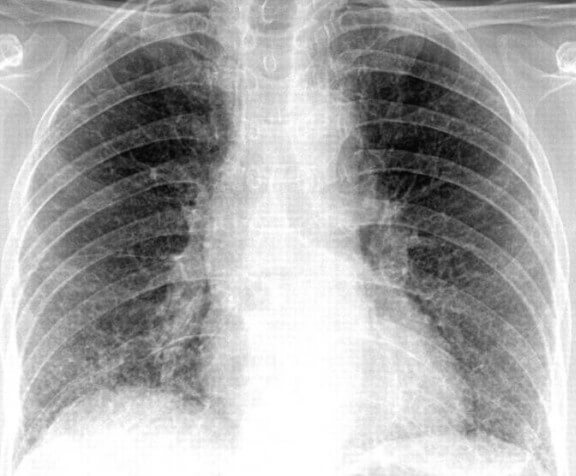

Чтобы правильно поставить диагноз, необходимо сдать кровь, мокроту для лабораторных исследований, и сделать рентген грудной клетки. Если диагноз поставлен правильно, врач назначает лечение антибиотиками. При пневмонии это самое верное средство лечения. Антибиотики при пневмонии помогают устранить очаг воспаления.Применение противомикробных препаратов необходимо, чтобы не допустить развитие болезнетворных организмов, бактерий, палочек, вирусов и свести к минимуму риск развития осложнений. Если своевременно не начать лечение, можно упустить время. Из-за этого последующее лечение может продлиться очень долго, а в некоторых случаях промедление приводит к летальному исходу.

Для лечения воспаления легких необходимо принимать антибиотики не меньше семи дней. После этого делают контрольный рентген грудной клетки, чтобы исключить наличие очага инфекции в легких. Если он будет обнаружен, повторяют курс лечения, но уже другим антибактериальным препаратом. В некоторых случаях возможна консультация у фтизиатра.Воспаление легких обязательно должно лечиться в стационаре. Самостоятельно, и часто неправильно подобранные антибиотики во многих случаях вызывают побочные эффекты, состояние больного может ухудшиться, повышается риск развития осложнений и ухудшается прогноз вылечивания пневмонии.

Для достижения максимально положительного эффекта от приема антибиотиков при пневмонии у взрослых врачи придерживаются правил их назначения. В первую очередь, при установлении рентгенологически подтвержденного диагноза «Пневмония» и до идентификации точного микробного возбудителя в мокроте пациента выписываются антибиотики широкого спектра активности. Это значит, что препарат будет охватывать своим лечебным эффектом целый спектр микробов. После того, как станет известен конкретный возбудитель, антибиотик можно изменить (если спектр активности не включает этого микроба).